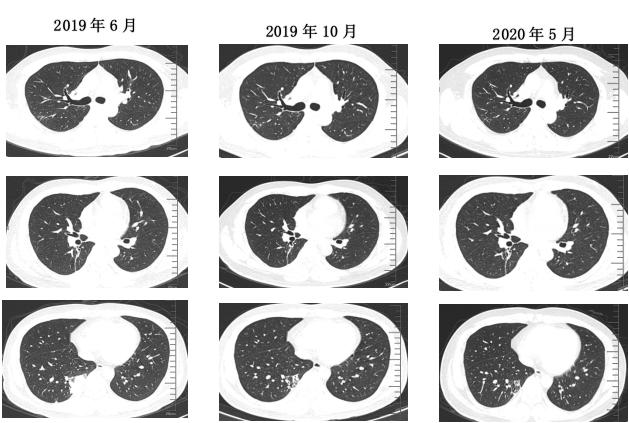

治疗后随访(胸部CT):

2021-2(停药7个月后)复查胸部CT:

1、疾病明确诊断并给予针对性治疗后,需要动态随访;治疗过程病灶先小后大,要注意警惕其他病原体的感染。